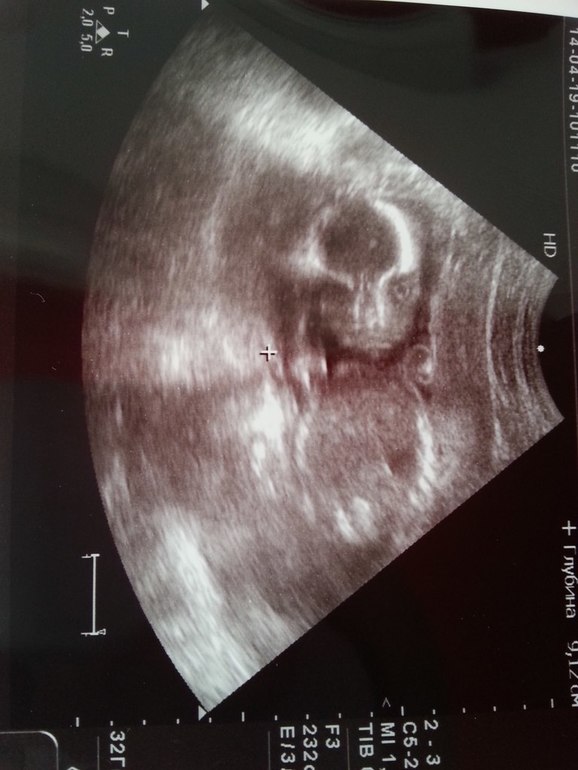

И вот личико нашего марсианина)

На животик выдавили добрую порцию геля и мы замерли в ожидании. На экране появилась наша малявка. Руки были за головой и так почти все узи, лишь под конец когда пытались померить нос, малыш начал ладошками прикрываться(кстати вышло 7,5 мм)) Весит наше чудо 363 г, все органы на месте и по размерам тоже все отлично.Идем практически срок в срок(по узи 20(+2) а по последним М 20(+3)). Но когда дело дошло до пола, то тут опять начались "проблемки".

Уже второй раз услышали от врача(причем от другого), что видно не очень хорошо и вроде как девочка, но совсем не точно, потому как мошонка и половые губы на таком сроке похожи. Да и малек не давал подобраться так, чтобы увидеть отсутствие или наличие писюна) Вот и остается мой киндер большим сюрпризом)